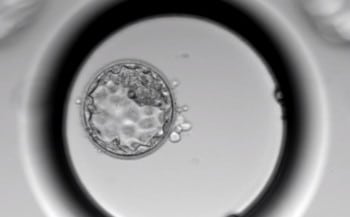

También cabe destacar el innovador incubador Time-Lapse-Geri, que posibilita una observación y valoración constantes de los embriones en el laboratorio. Este método aporta grandes ventajas, como la monitorización continua de los embriones, la mejora de la selección embrionaria, el aumento de la tasa de embarazo por transferencia y la reducción de la tasa de embarazo múltiple, ofreciendo un control personalizado de cada uno de ellos.

“La optimización en la selección embrionaria orienta gran parte de los esfuerzos de los laboratorios de los centros de fertilidad”, afirma la embrióloga María Hebles, responsable de laboratorio de Ginemed Sevilla. “Sin duda, resulta vital disponer del mejor incubador para cuidar los embriones, que además permite hacer la mejor selección sin interferir en ningún momento en el desarrollo del embrión”, continúa.